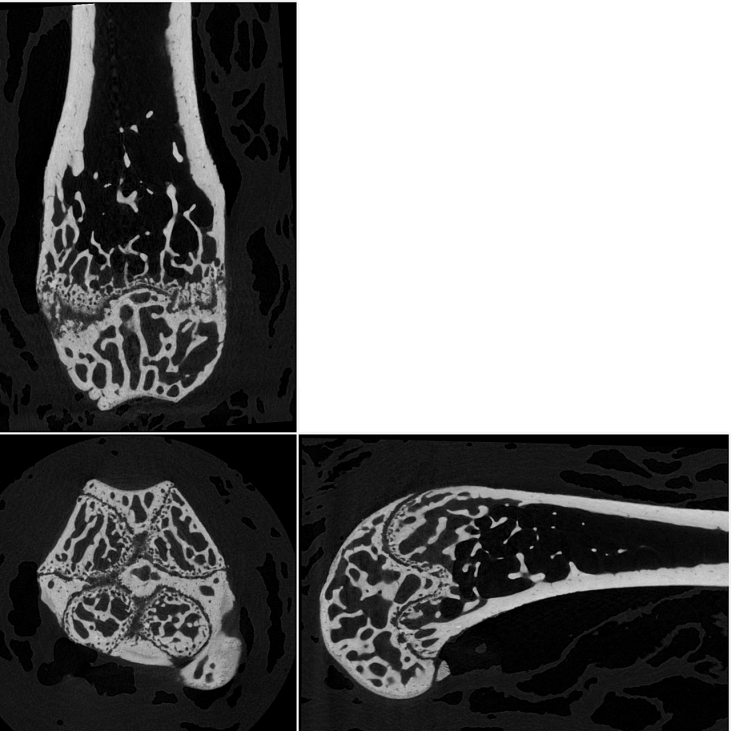

8. Orthogonal slices through a mouse femur, scanned at 2.8 umvoxel size.

8.png